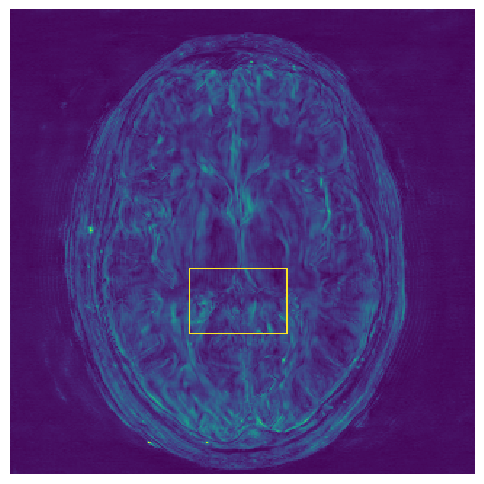

Figure 3: Reconstructions results. Rows 1 and 3: Examples of comparing the ground truth (GT) fully sampled image to the reconstructed images obtained by the three models (1-3), NPB-REC, baseline, E2E-VarNet trained with Dropout, and the NPB-REC std. map at accelerations R=4𝑅4R=4, R=8𝑅8R=8, respectively. Rows 2 and 4: The corresponding annotated ROIS of Nonspecific white matter lesions.

Fig. 3 presents examples of reconstruction results obtained by (1) our NPB-REC approach, (2) the baseline, and (3) Monte Carlo Dropout, for equispaced masks with two different acceleration rates R=4𝑅4R=4 and R=8𝑅8R=8. The reconstructed images predicted by the three models are smoother than the reference image. This is due to the fact that all the models were trained with SSIM loss, which tends to produce overly smooth reconstructions while preserving the diagnostic content and the anatomical features Sriram et al. (2020a). These images can be enhanced by dithering the image by adding a small amount of random Gaussian noise to produce a more textured reconstruction, as proposed in Sriram et al. (2020b).

Table 1 presents the mean PSNR and SSIM metrics, calculated over the whole inference set, for the three models. Our NPB-REC approach achieved significant improvements over the other methods in terms of PSNR and SSIM (Wilcoxon signed-rank test, pmuch-less-than\ll1e-4, except for SSIM values in line W, R=4𝑅4R=4 where they are roughly the same for NPB-REC and Baseline). The improvement in the reconstruction performance can be noted both quantitatively from the metrics, especially for masks with acceleration rate R=8𝑅8R=8, and qualitatively via the images of annotations, where our results show less smoothness than those obtained by Dropout.

5.2 Uncertainty Assessment

We calculated the mean value of the std. maps, obtained by our method and the Monte Carlo Dropout method, for all images in the inference set and utilized it as an uncertainty measure. The correlation between these uncertainty measures and reconstruction error (MSE) is depicted in Fig. 4. Our NPB-REC uncertainty measure exhibits a higher correlation with the Reconstruction error compared to Dropout (Pearson correlation coefficient of r=0.93𝑟0.93r=0.93 vs. r=0.89𝑟0.89r=0.89). Further, fig. 4LABEL:sub@fig3:c demonstrates our uncertainty measures correlate better with the acceleration rates used during acquisition. These outcomes, in turn, indicate the ability of our uncertainty measure to detect unreliable reconstruction performance. It is worth mentioning that the strong linearity of the correlation exhibited was preserved even for higher acceleration rates and when we repeated the same experiments on the knee test set (in all cases we obtained r>0.92𝑟0.92r>0.92).